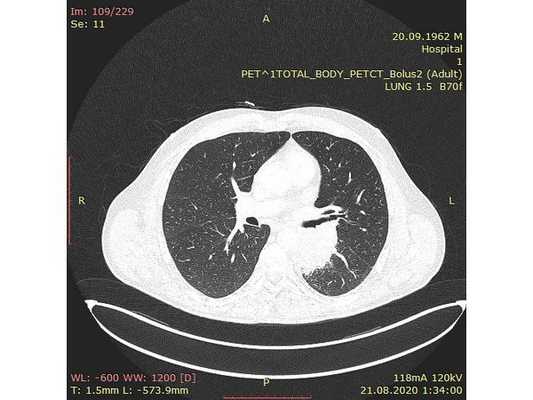

31.07.2020 мужчина 57 лет обратился в Клиническую больницу № 2 АО ГК МЕДСИ с данными компьютерной томографии, где выявлено центральное новообразование в корне нижней доли левого лёгкого.

Чтобы провести первичное стадирование опухоли, пациенту проведена позитронно-эмиссионная томография в сочетании с компьютерной томографией (ПЭТ-КТ). По данным исследования, выявлена метаболически активная опухоль в корне левого лёгкого с бугристыми контурами размерами 41 х 43 мм. В толще опухоли проходят нижнедолевой бронх и бронх 6-го сегмента левого лёгкого, просветы бронхов значительно сужены. Нижняя доля левого лёгкого уменьшена в размерах за счёт того, что сегменты 6, 9 и 10 субтотально (частично) инфильтрированы и безвоздушны. Лимфатические узлы корня лёгкого и средостения не увеличены в размерах и не накапливают радиофармпрепарат (РФП), который был введён пациенту перед обследованием внутривенно. Других очаговых образований и очагов гиперметаболизма в организме не обнаружено.

При этом отмечено, что опухоль распространяется в средостение по нижней стенке левого главного бронха и широко прилежит к нижнегрудному отделу аорты (по заключению специалиста ПЭТ-КТ — имеется инвазия опухоли в ткани средостения и возможное врастание в стенку аорты). При самостоятельном пересмотре изображений отмечено, что "опухолевая" ткань, которая распространяется по нижней стенке левого главного бронха в средостение, не накапливает РФП (т. е. не является злокачественной), а стенка аорты в области "инвазии" опухоли имеет ровный чёткий контур и адвентициальную границу, что также свидетельствует об отсутствии онкологического процесса в этой области.

Основное заболевание: Центральный немелкоклеточный рак нижней доли левого лёгкого, сT2bN0M0, IIА стадия. (T2b — опухоль более 5 см, но менее 7 см в наибольшем измерении; N0 — нет метастазов в региональных лимфатических узлах; M0 — нет отдалённых метастазов).

КТ ОГК. Солидная мягкотканная опухоль в верхней доле левого легкого с морфологическими признаками злокачественности.